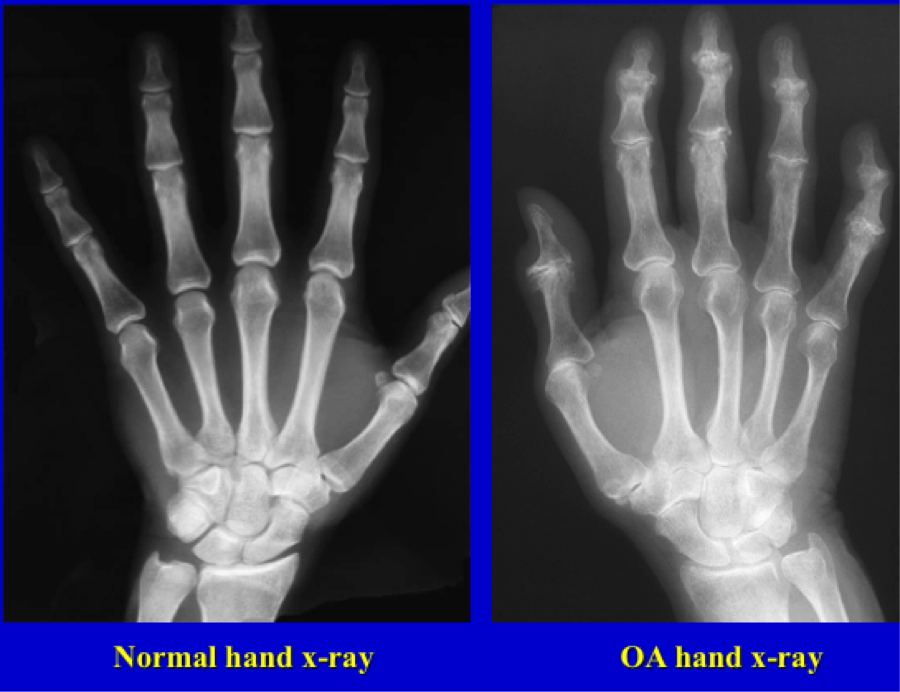

OA: what is seen on imaging?

which joints does OA most commonly affect?

hands, hips, knees

Hand involvement with OA: distribution by gender? which joints most affected?

-Females 4x more likely to have hand involvement than men (more freq found post-menopause). especially basilar thumb joint (first carpometacarpal - CMC).

-Male: wrists more common (possibly occupation-related)

-Both: DIP, PIP